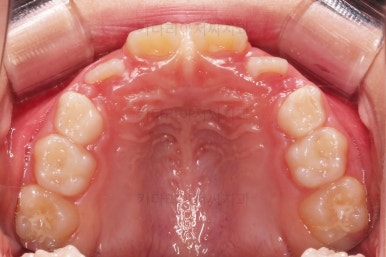

초진 시 입안의 모습입니다.

아래쪽 치열이 전반적으로 윗니보다 앞쪽에 위치한 전형적인 앵글씨 3급 부정교합인데요.

어금니에서부터 앞니까지 아랫니가 윗니보다 앞쪽에 위치하네요.

특히 앞니는 아랫니가 윗니보다 나와있는 "반대교합" 상태였고요.

또한 위아래로 겹침이 없고 떠있는 "개방교합" 상태였어요.

즉, 앵글씨 3급 부정교합 - 반대교합 - 개방교합 등 굉장히 복합적인 교합의 문제를 가진 환자였습니다.